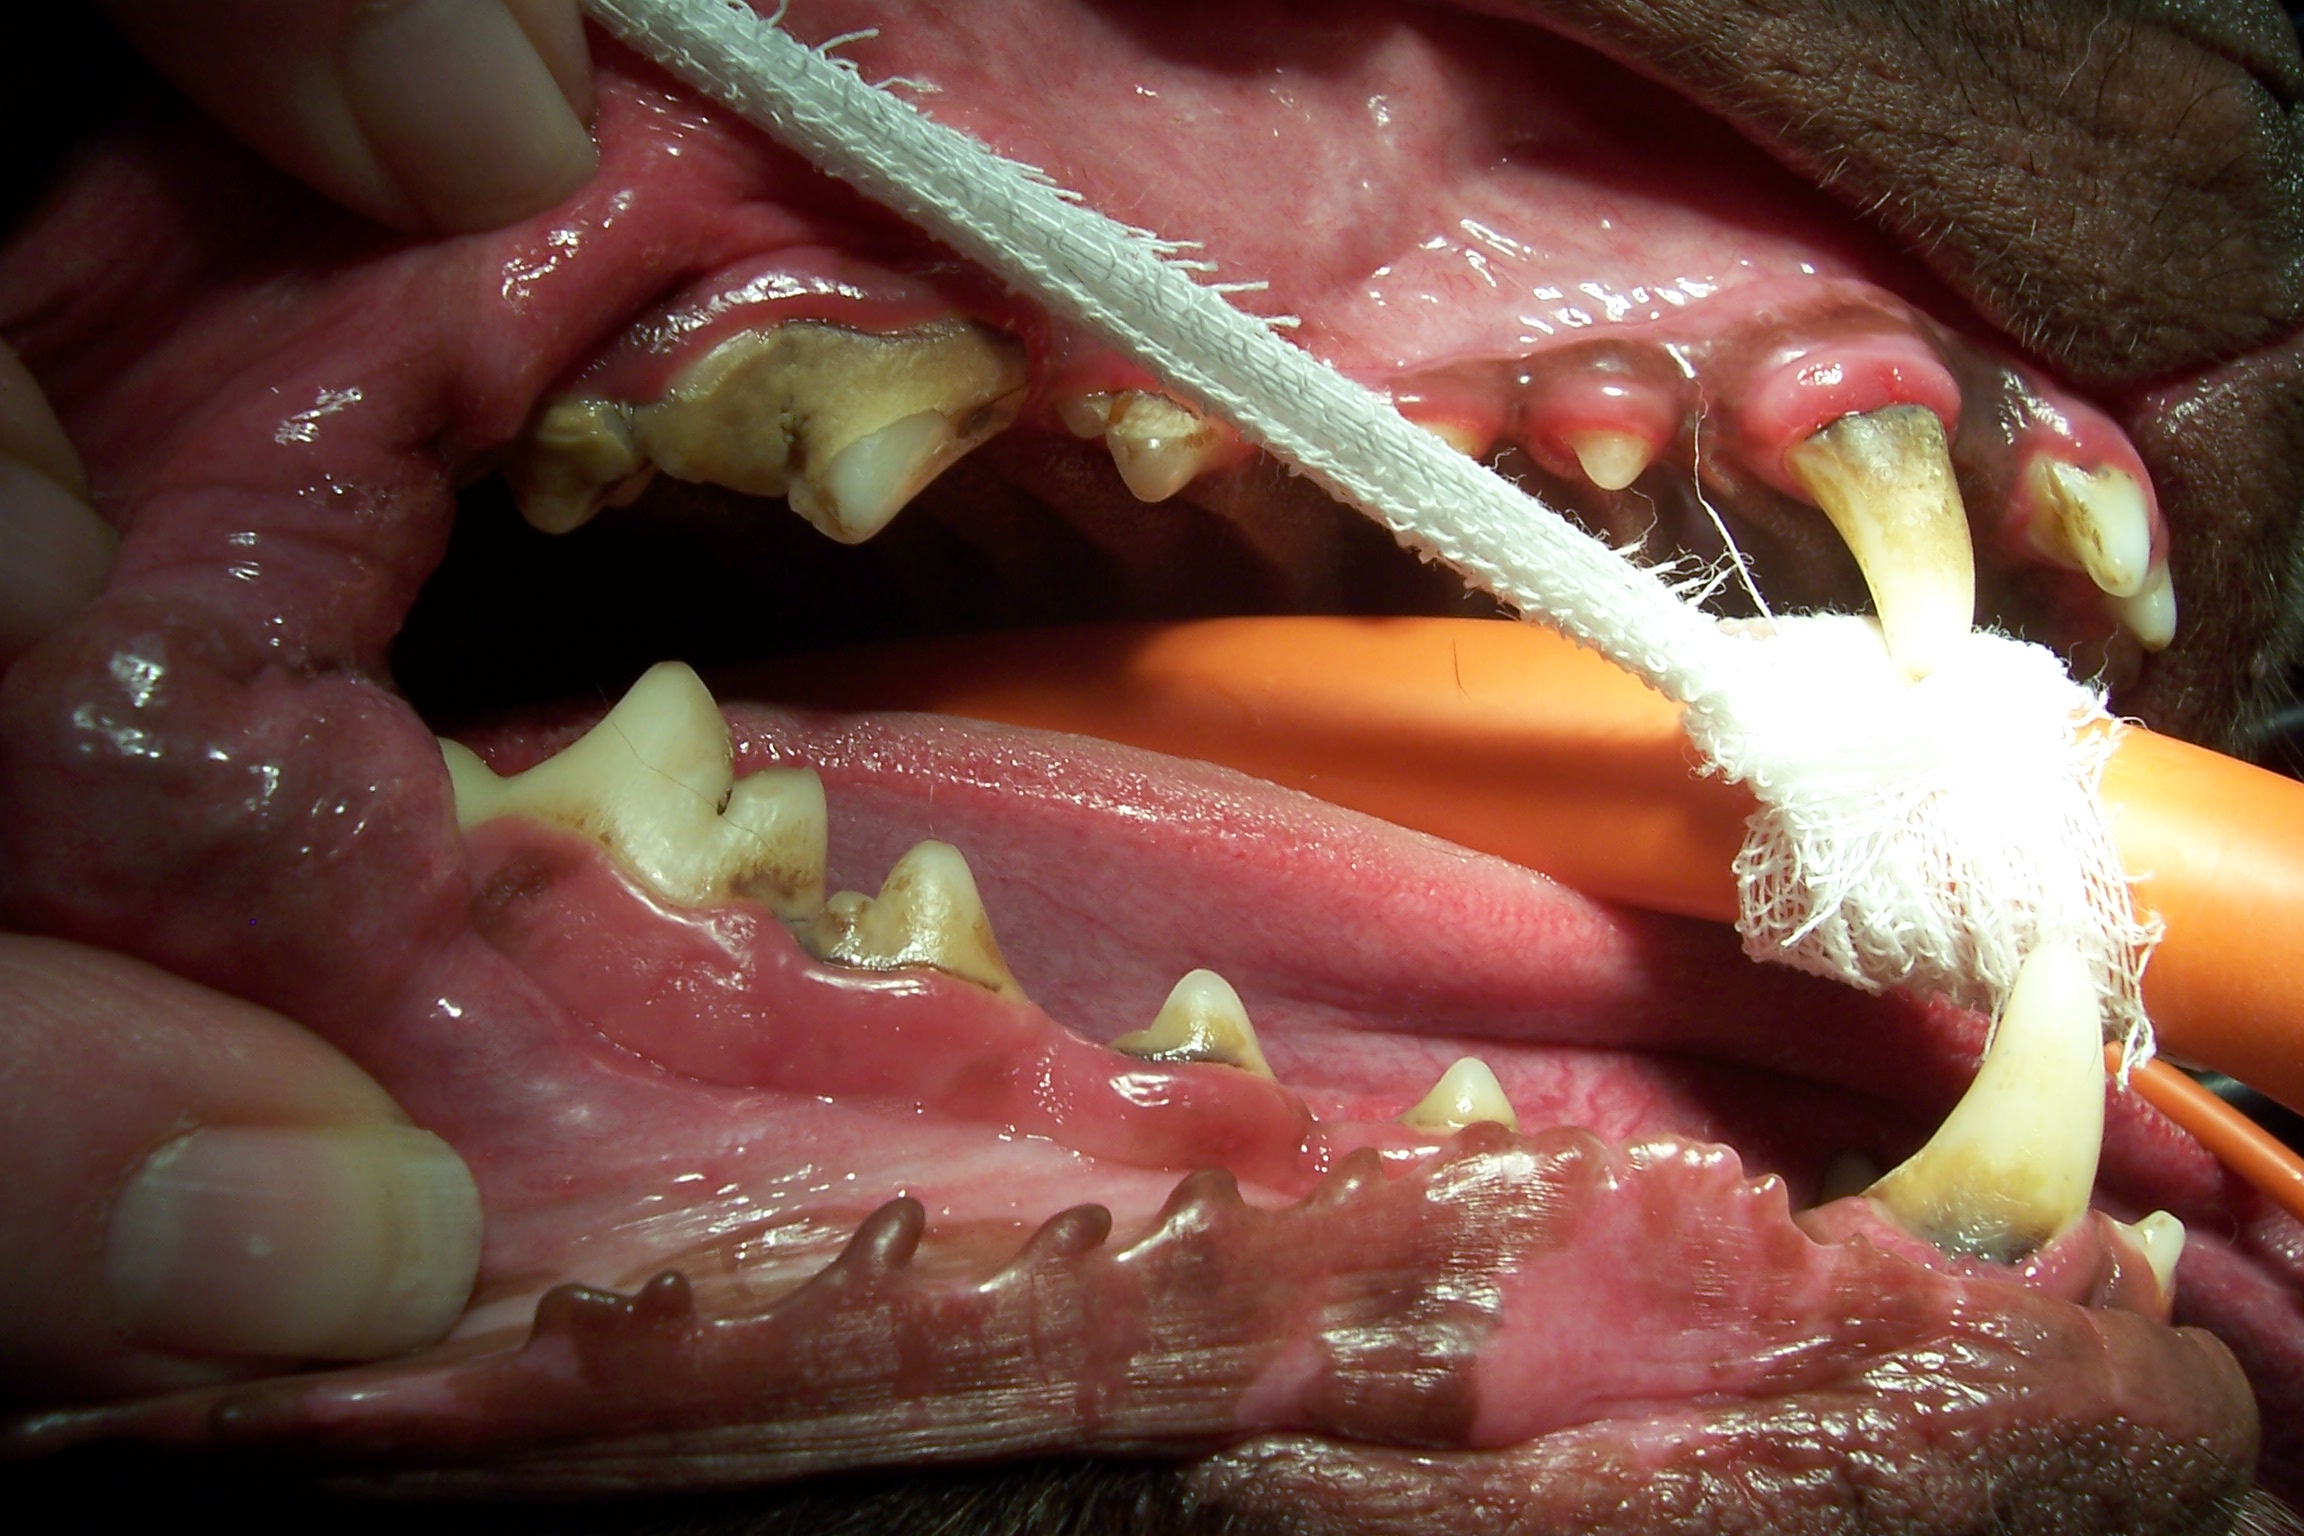

Healthier mouth after dental cleaning

-